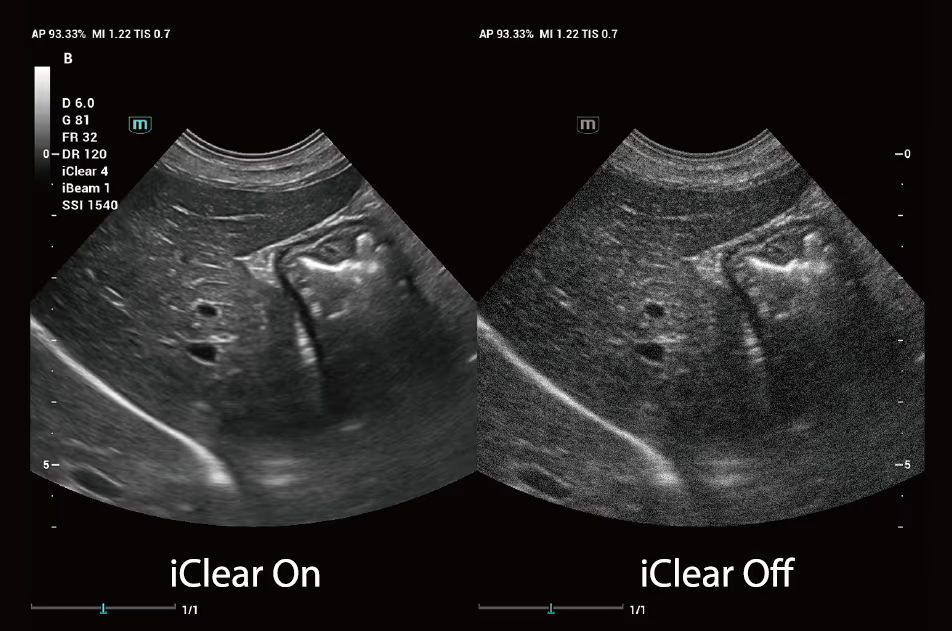

Bu akıllı görüntü optimizasyon teknolojisi, 2 boyutlu görüntülerdeki benek gürültüsünü etkili bir şekilde bastırır, görüntü kontrast çözünürlüğünü artırır ve doku sınırlarını daha net, yankıları ise daha hassas hale getirir.